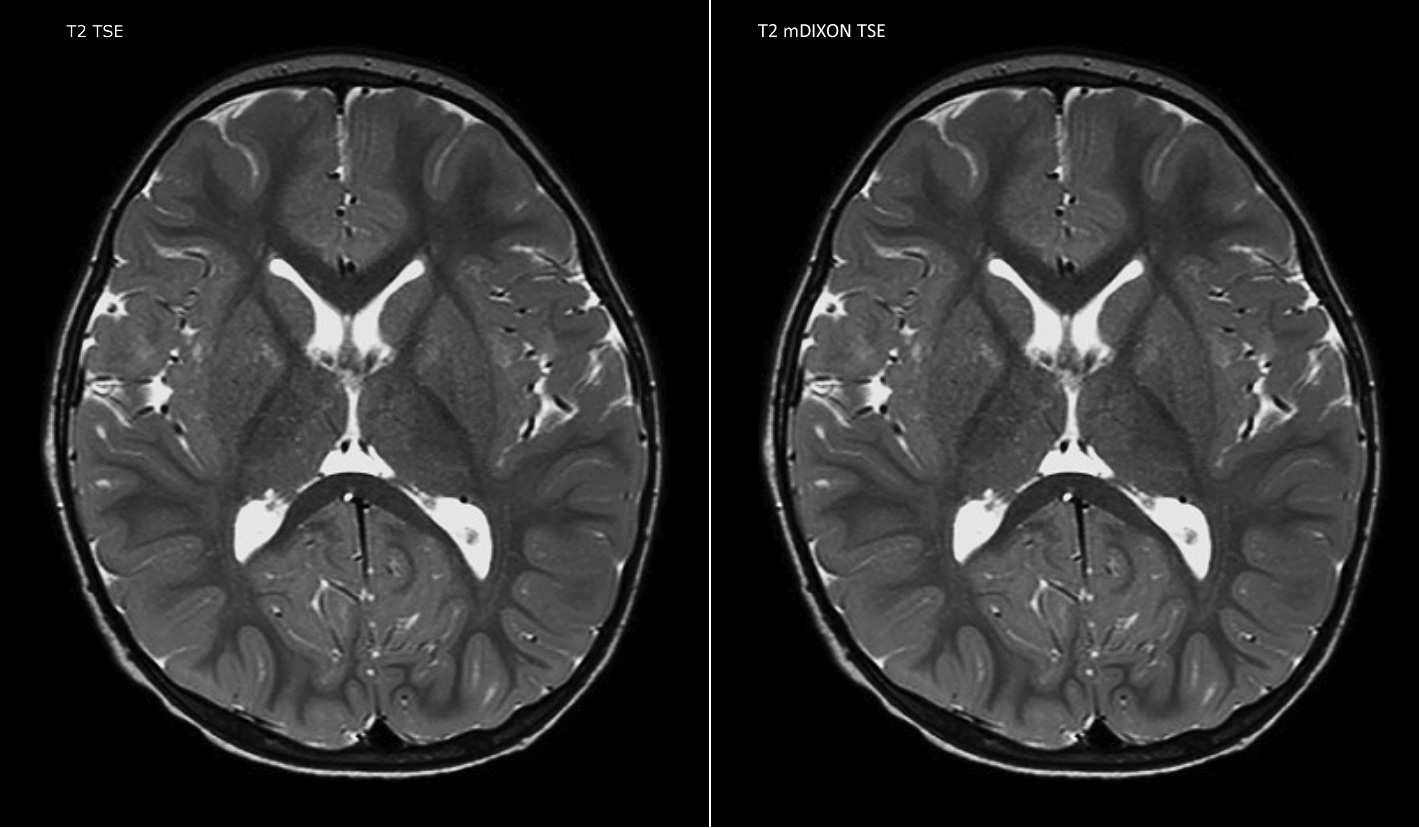

Philips mDIXON TSE is a two-point DIXON technique that separates water and fat signals, for time-efficient fat-free imaging, even in challenging neuro anatomy.

“mDIXON TSE has been one of the most significant improvements in imaging sequences that we have utilized to date at PCH,” says Dr. Miller. “Its multi-parametric acquisition allows us to obtain fat suppressed images and equivalent non-fat suppressed T2 images all in the same sequence. In addition, prior methods of fat suppression could be artifactually corrupted by poor patient anatomy or poor operator application, but with mDIXON we now have a robust and reliable method of fat suppression.”

Fat saturation is historically challenging at the ends of fields of view, especially in total spine imaging and in difficult patient anatomy such as the lower regions of the neck. “Due to the unique fat suppression capabilities of mDIXON, however, these challenges no long apply,” says Dr. Miller. “We routinely obtain homogeneous fat suppression under virtually all conditions. It has also led to some efficiencies by not having to repeat sequences because of that technical failure.”

mDIXON TSE makes a difference

“mDIXON TSE is most useful in patients with lesions or abnormalities in the soft tissues such as the face and neck, and for patients with contrast enhancing abnormalities that are mostly visible with fat suppression,” says Dr. Miller. “All our spine imaging now routinely contains mDIXON water-only T2 images, and this allows us to identify pathology that may be obscured by non-fat suppressed imaging such as injuries of the bone. And it’s not necessary to obtain additional standard TSE T2 images because the in-phase mDIXON images are equivalent to standard TSE T2 images.”

“mDIXON TSE has increased our diagnostic confidence in ruling in or ruling out abnormalities in which fat suppression is critical to diagnosis, such as metastatic disease or osseous abnormalities.”